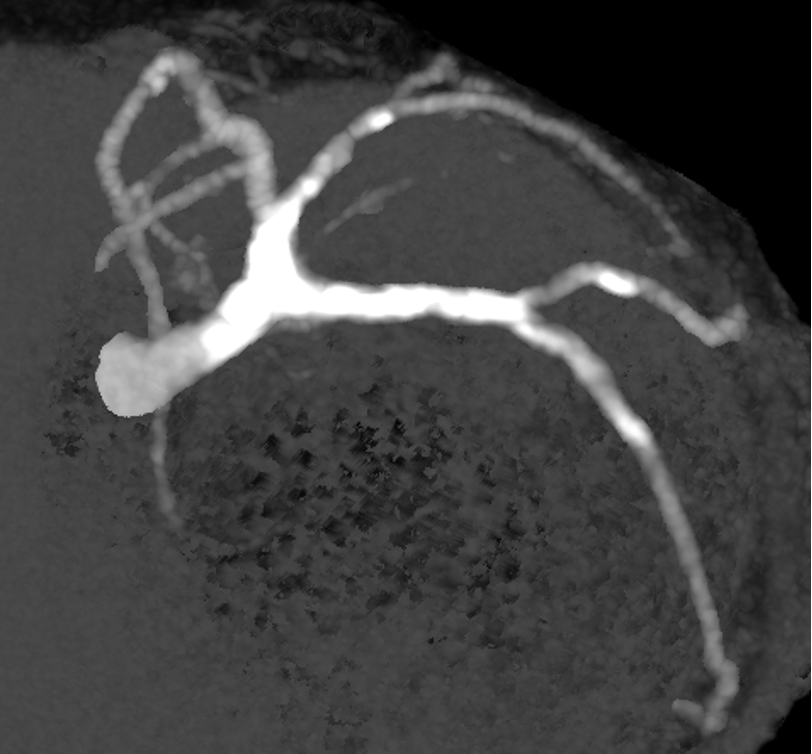

LCA CAG

-

Coronary CT